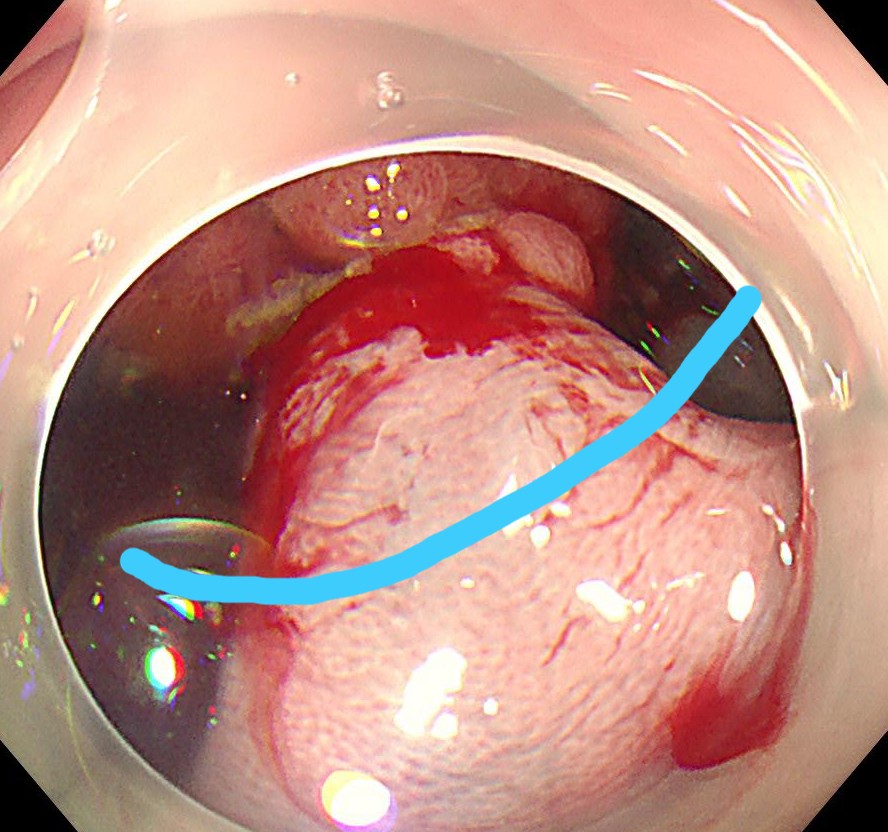

横行結腸に1型の腫瘍を認めます。

ピットパターンはおおむねIII型ですが、腫瘍基部と中心陥凹部はV型であり、早期の大腸がんが疑われます。